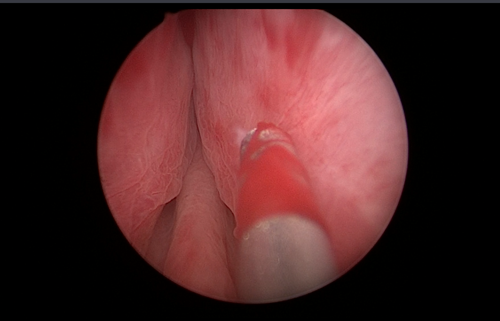

通过显示器可见,前列腺中叶腺体明显凸起,两侧叶腺体明显肥大,将尿道内口几乎完全堵住,再缓慢进入膀胱,见前列腺已突入膀胱,压向膀胱三角区。潘斌在内镜下确定精阜位置后进行精准剜除,再使用组织粉碎器进入膀胱后将术中切下的前列腺组织粉碎,然后经负压吸引至体腔外。再仔细检查前列腺窝,观察创面是否止血彻底。术毕留置导尿管,见尿管颜色清亮。